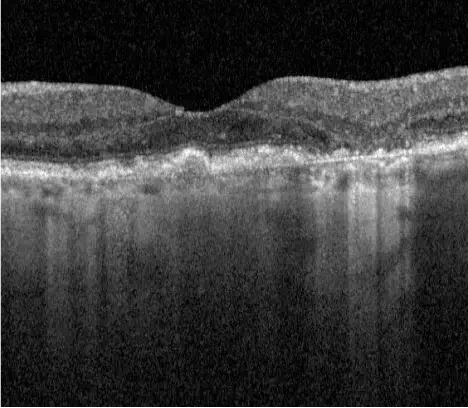

Neovascular AMD

- In clinical trials, use of IZERVAY was associated with increased rates of neovascular (wet) AMD or choroidal neovascularization (7% when administered monthly and 4% in the sham group) by Month 12. Over 24 months, the rate of neovascular (wet) AMD or choroidal neovascularization in the GATHER2 trial was 12% in the IZERVAY group and 9% in the sham group. Patients receiving IZERVAY should be monitored for signs of neovascular AMD.